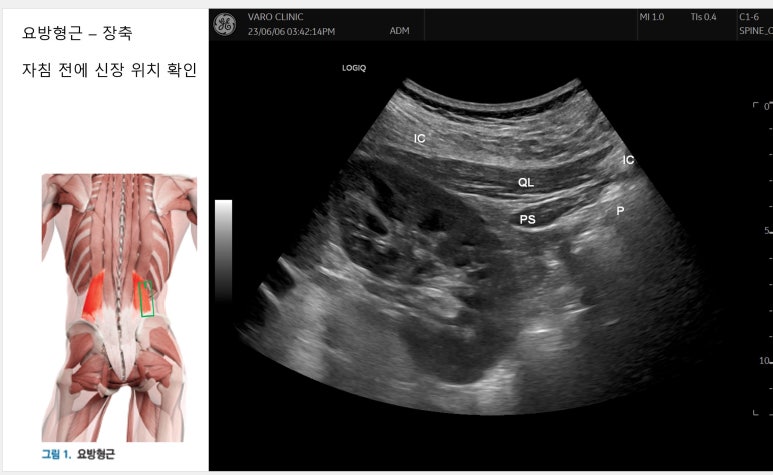

허리 디스크 탈출증으로 내원한 환자를 대상으로 족태양경근을 촉진하여 민감한 통증이 재현되는 아시혈에 시술할 때 신장의 위치를 초음파로 미리 확인하고 자침하는 것이 안전합니다.

사람마다 장기의 위치가 다양해서 초음파 영상으로 관찰한다면 좀 더 정확한 치료를 할 수 있거든요.